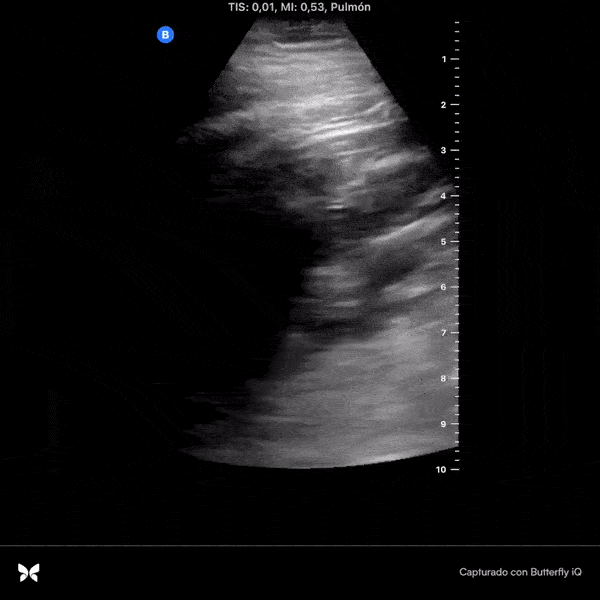

Day 1 after #COVID diagnosis. Sore throat, headache (strong!), dry cough but not shortness of breath. No lung US abnormalities. Will keep a #POCUS track of my lungs. @yaletung